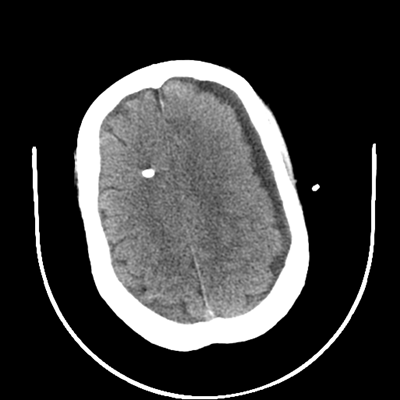

The patient goes down to CT. The following images are obtained. The subdural fluid collection is stable, as is the ventricular caliber.

Starting with the non-contrast head CT, we can appreciate that there's actually not much residual subarachnoid blood at all; it's essentially all resorbed already (and cleared through the EVD). The ventricular caliber is stable. With the CTA head (for convenience's sake, the MIPs were shown), it's subtle, but we can see that the PCAs on each side are not as smooth and regular. The right MCA, starting at the bifurcation, also becomes narrower. This is [radiographic] vasospasm. Now, looking at the CT perfusion-- specifically, the Tmax (MTT) map that were selected-- there's clearly some abnormality within the bilateral cerebellar hemispheres and occipital lobes. Not a lot, but it's there. Delving further into this map, we can appreciate that the areas of abnormality are mainly green, signifying that these areas have Tmax > 6 seconds. This is the threshold that is specific, not sensitive, for vasospasm.

Yes! It does. The patient had a decline in level of consciousness with diffuse loss of motor function. This does correlate to the basilar territory. (Alternatively, bilateral MCA vasospasm could also be responsible, reminding us that a decline in consciousness could technically be focal/multifocal.) Thus, we can say that this patient does have clinical vasospasm. Whether this will develop into irreversible DCI remains to be seen; at least, the non-contrast head CT and the other portions of the CT perfusion (not shown) currently don't [yet] suggest infarction.